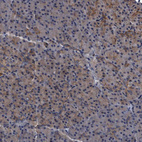

Immunohistochemical staining of human lymph node shows very strong cytoplasmic positivity in germinal center cells.